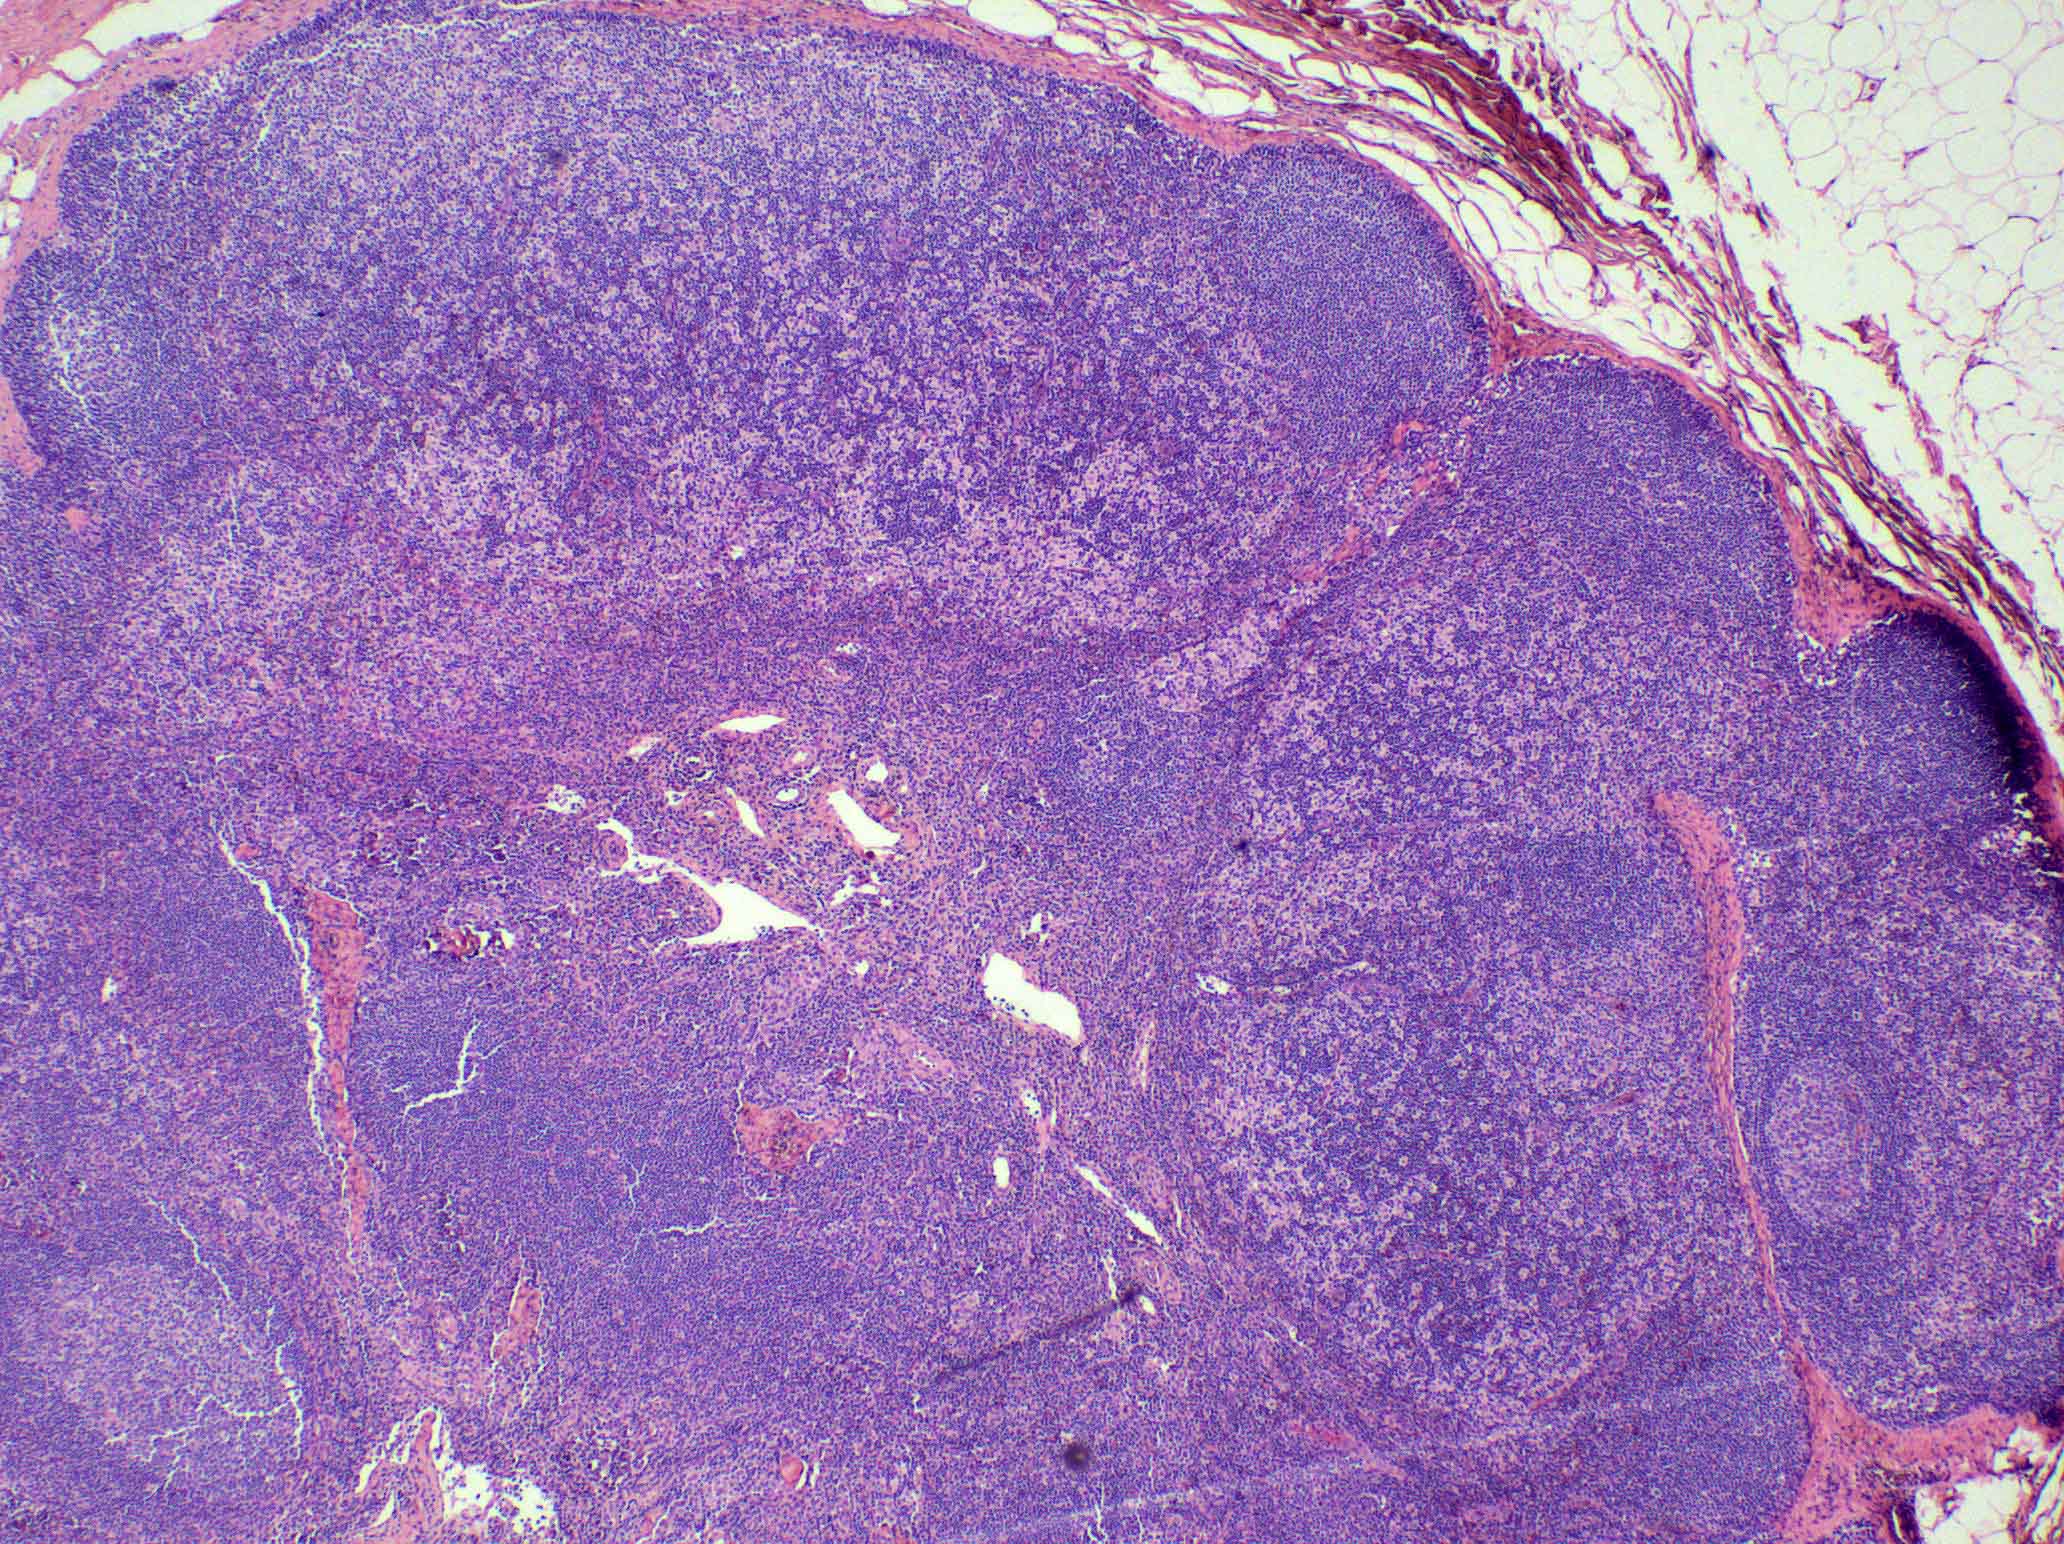

Microscopic (histologic) description

- There is always preserved nodal architecture with intact capsule

- Follicular hyperplasia may be present but it is usually minimal

- Spectrum of changes from mild to severe, characterized by paracortical expansion with pale, irregularly shaped areas containing numerous pale staining histiocytes, interdigitating dendritic cells, Langerhans cells and occasional immunoblasts

- Predominance of interdigitating dendritic cells over Langerhans cells, which are indistinguishable on morphology alone

- Both cell types show ill defined cell borders with fine irregular reniform nuclear contours and occasional nuclear grooves

- Paracortical or sinusoidal histiocytes and macrophages often contain cytoplasmic melanin pigment but they also can contain hemosiderin or lipid

- Medullary plasmacytosis is variable

- Distended sinuses with histiocytes, plasma cells and eosinophils can be present

- Variable, usually mild capillary hyperplasia

- Mild / early

- Increased interdigitating dendritic cells that do not form nodules or networks, admixed with Langerhans cells and histiocytes

- Hyperplastic lymphoid follicles

- Severe / florid

- Large vague nodules or sheets of interdigitating dendritic cells that can compress lymphoid follicles

- Rarely, sinuses can be partially compressed

- Severe forms are more frequently seen in patients with mycosis fungoides

Microscopic (histologic) images

Contributed by Ingrid Tam, M.D., M.Sc., Emina Emilia Torlakovic, M.D., Ph.D. and Nikhil Sangle, M.D. (Case #396)